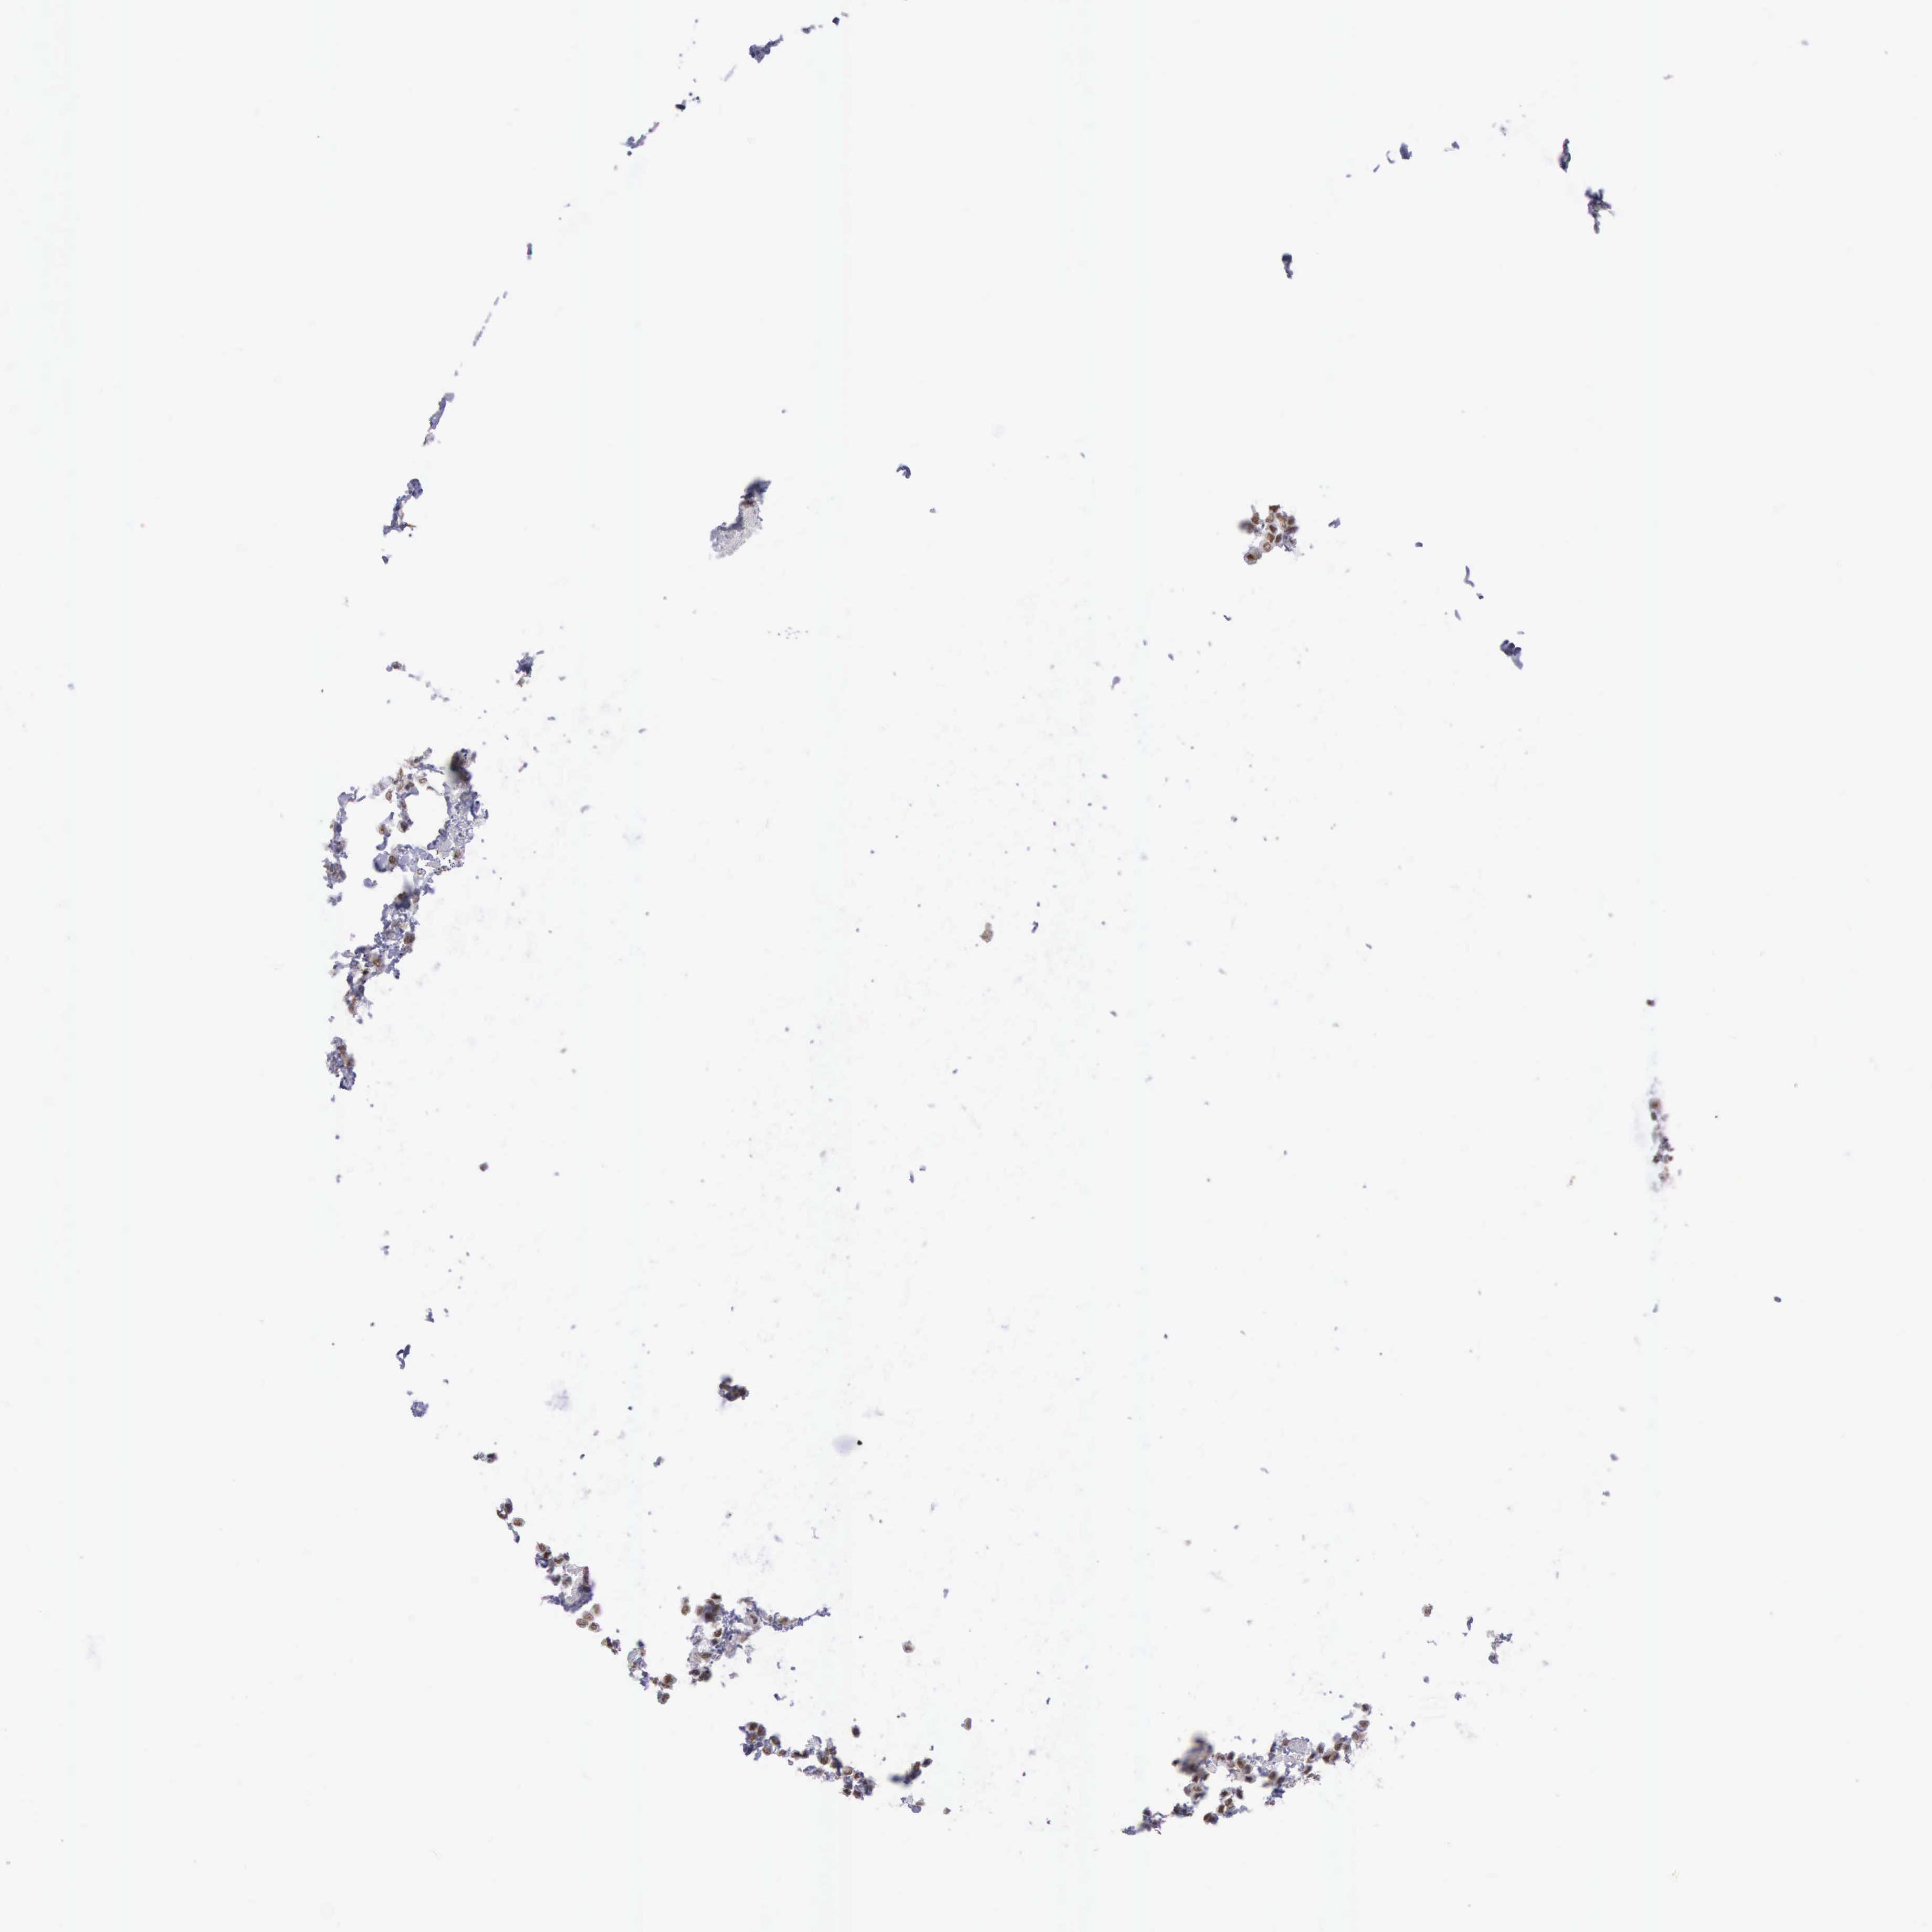

BRCA TCGA BRCA VALIDATION PROTEIN EXPRESSION

Breast cancer

Human cancer